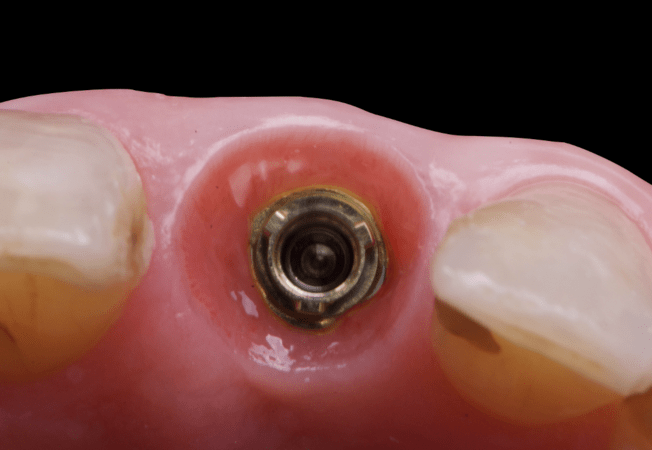

On the same day as the surgery, an immediate-load provisional crown was delivered. This restoration was fabricated in acrylic resin and screw-retained on the implant, following the “one abutment one time” principle. The provisional crown was carefully adjusted to avoid occlusal loading while supporting the peri-implant soft tissue architecture during the healing phase.

The provisional not only satisfied the patient’s functional and esthetic demands but also played a key role in shaping the emergence profile and conditioning the gingival margin. By providing a provisional solution immediately, the patient was able to leave the clinic with a natural-looking smile, avoiding any psychological or social impact associated with tooth loss in the anterior maxilla.